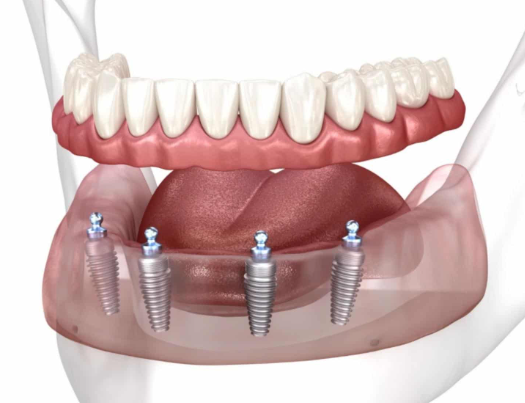

3、植入種植體: 在局部麻醉下,醫生通過微創技術準確地將鈦合金種植體植入牙槽骨。這個過程通常持續1-2個小時,具體時間取決於個體差異。

5、安裝基臺及牙冠(牙套): 當確認植體已成功癒合時,醫生將在其上方安裝基臺,然後根據顧客的具體需要製作和安裝牙冠(牙套)。